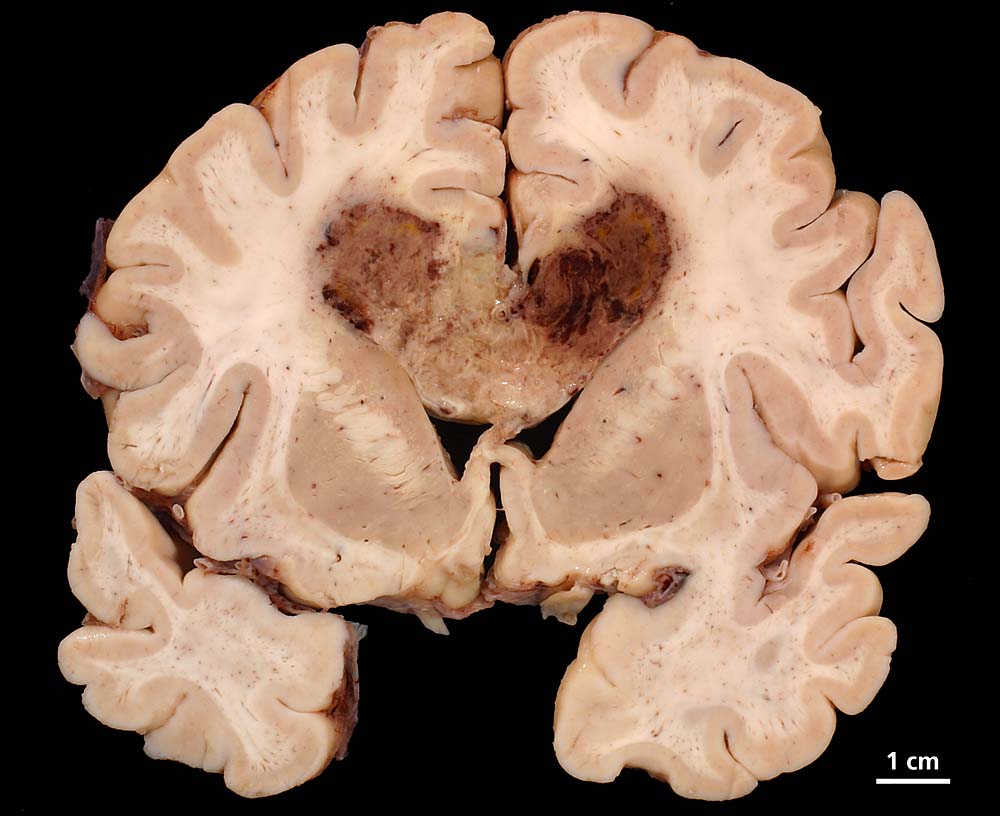

Lokalisation:

Bevorzugte Lokalisationen sind das Marklager des Frontal- und Temporallappens. Glioblastome des Hirnstammes sind selten und betreffen meist Kinder. Von dort breiten sie sich oft über den Balken schmetterlingsförmig auf die Gegenseite aus. Weniger als 5% der Tumoren wachsen multizentrisch. Eine Aussaat in den Subarachnoidalraum mit Metastasierung über den Liquor findet sich selten. Noch rarer sind hämatogene Metastasen in extraneurale Organe.

Morphologie:

Die Schnittfläche ist auffallend bunt. Dies ist bedingt durch ein Nebeneinander von graurotem vitalem Tumorgewebe, gelben Nekrosen, roten Einblutungen und gelegentlich grünlichen Gallertzysten.